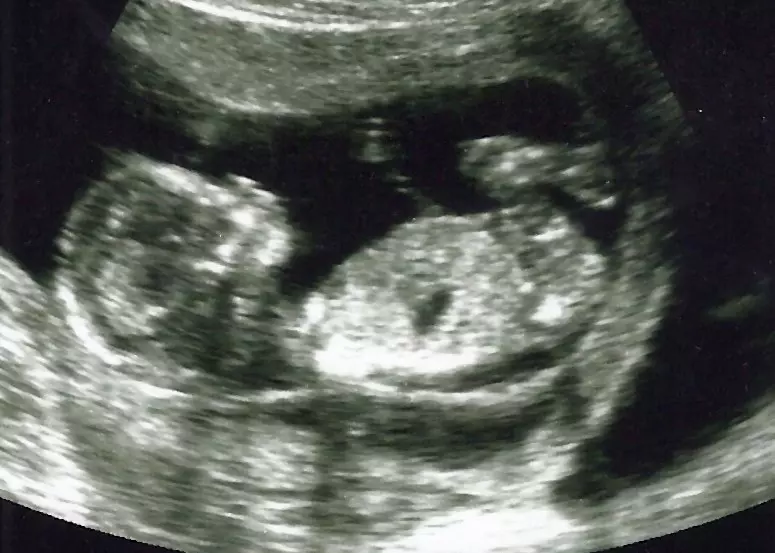

As early as six weeks, a “flickering” can be seen in the embryo of a pregnant woman at the time of an ultrasound. This cardiac activity, or heartbeat, affirms the presence of life within the womb. A common question asked of any pregnant patient following a visit to her obstetrician is, “Did you get to see your baby’s heartbeat?” thereby affirming the belief that life actually does exist in the womb.